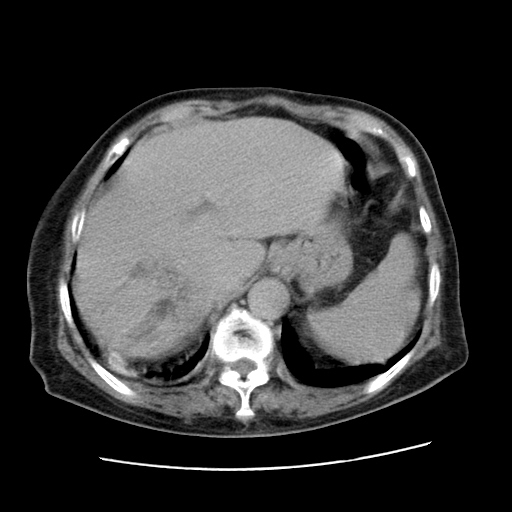

标题: CT25203:上腹部增强,看看

女,77.无不适

胆管扩张,壶腹部占位?

肝脏变异、异位胆囊,肝右叶肝内胆管结石并肝内胆管扩张。

肝内胆管扩张,胆囊炎,胆囊窝积液。 右侧胸腔少量积液。

肝右叶肝内胆管结石并肝内胆管扩张。

肝脏变异

肝右叶肝内胆管结石并肝内胆管扩张

胆总管扩张

肝右叶肝内胆管结石并肝内胆管扩张。胆总管下段梗阻,考虑壶腹部占位。

右侧肝内胆管局限性扩张,其内密度不均匀,扩张的胆管壁增厚,考虑肝内胆管炎合并结石可能性大

肝右叶肝内胆管结石并肝内胆管扩张。胆总管下段梗阻,考虑壶腹部占位。支持